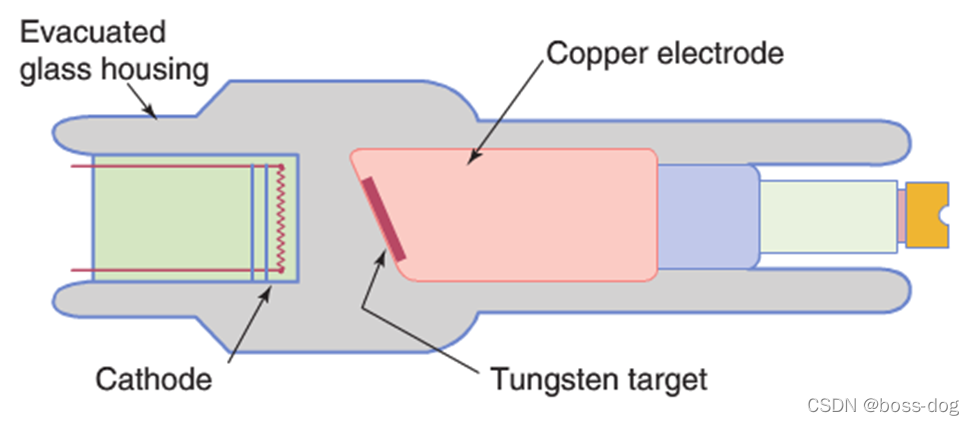

上图中为固定阳极x射线管(简易):(能量低,电流小)

主要用于①乳腺钼靶X光成像②牙科X光成像③小动物成像